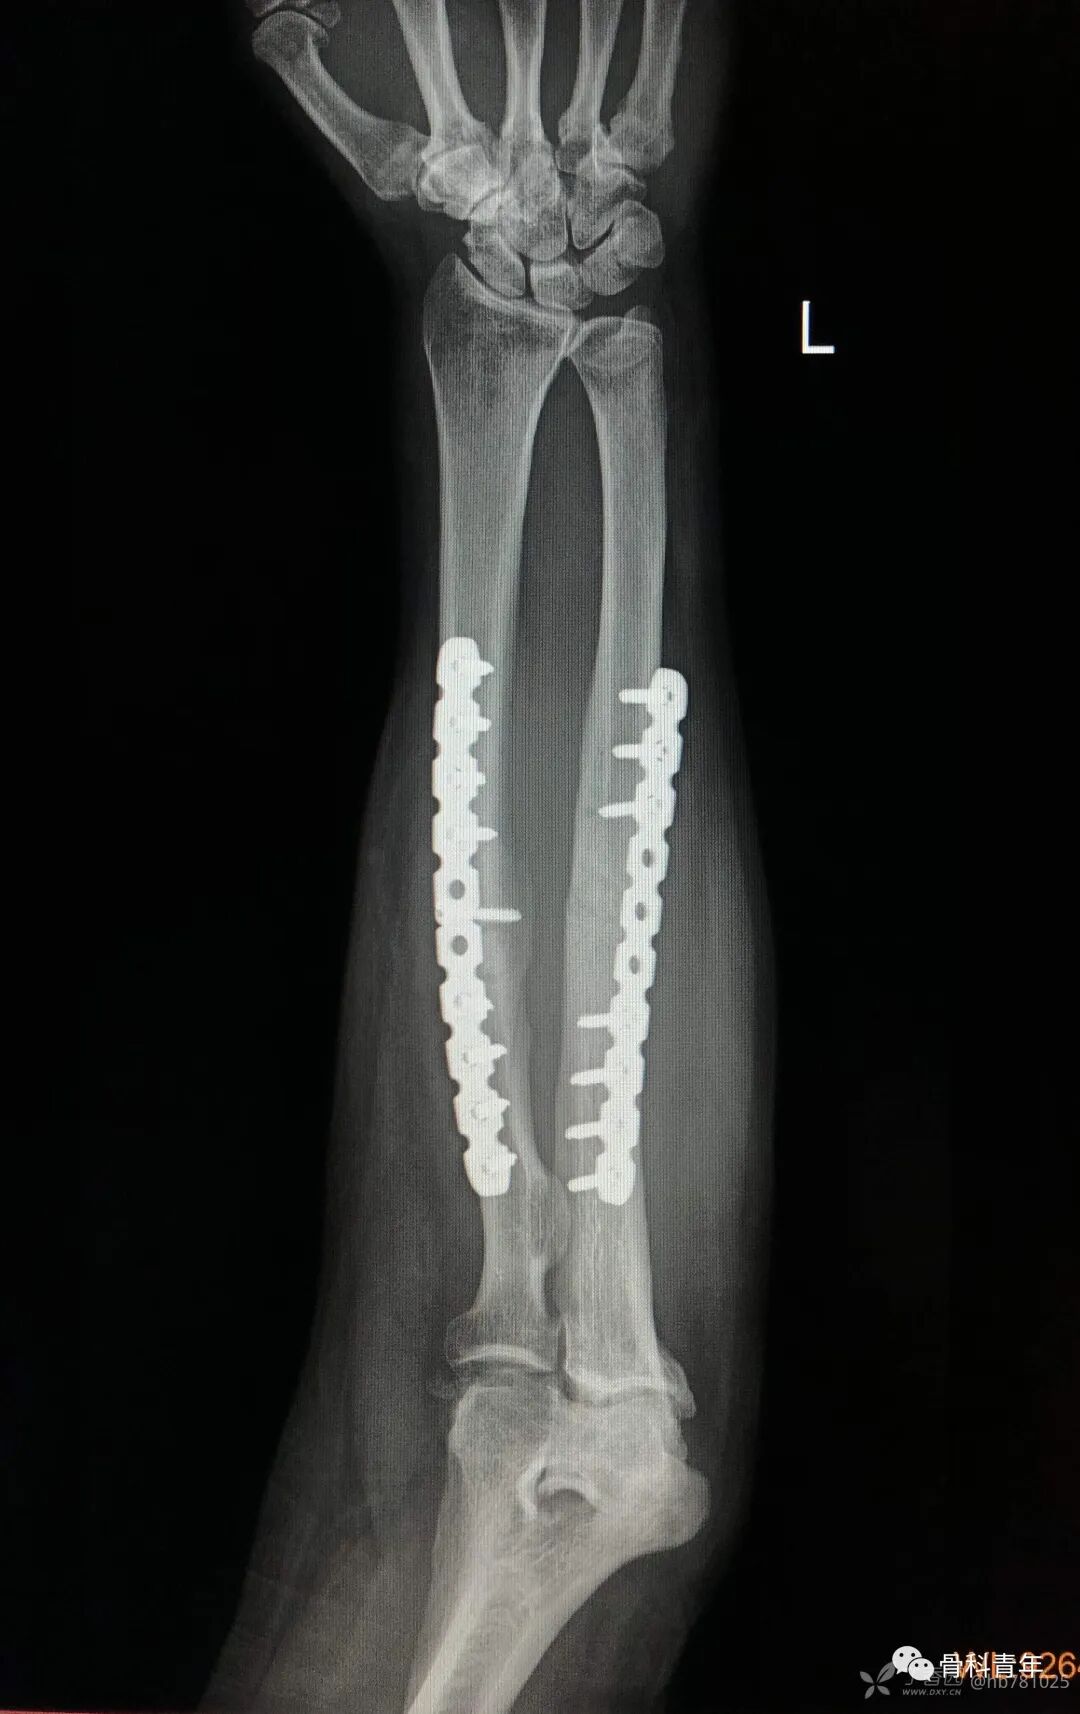

25.尺桡骨双骨折